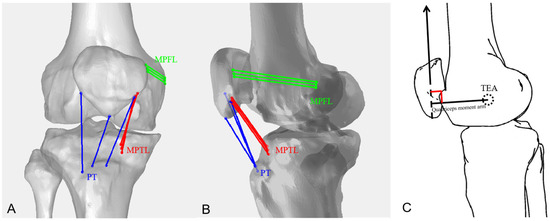

Length Comparisons of Each PT, MPTL, and MPFL Bundle